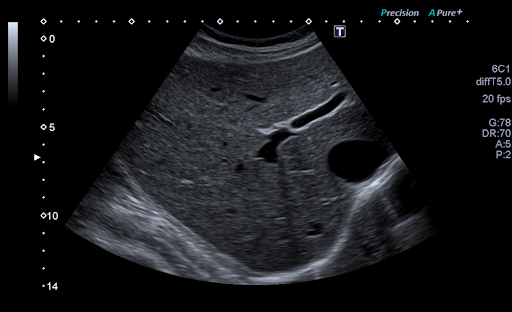

Технология Precision Imaging улучшает определение границ и делает края структур более четкими.

D-THI - Differential Tissue Harmonic Imaging - Дифференциальная тканевая гармоника

Увеличивает контрастность и пространственное разрешение на больших глубинах и у пациентов с плохой визуализацией.

Технология ApliPure+ позволяет достигать беспрецедентной однородности и детализации при сохранении клинически значимых маркеров.